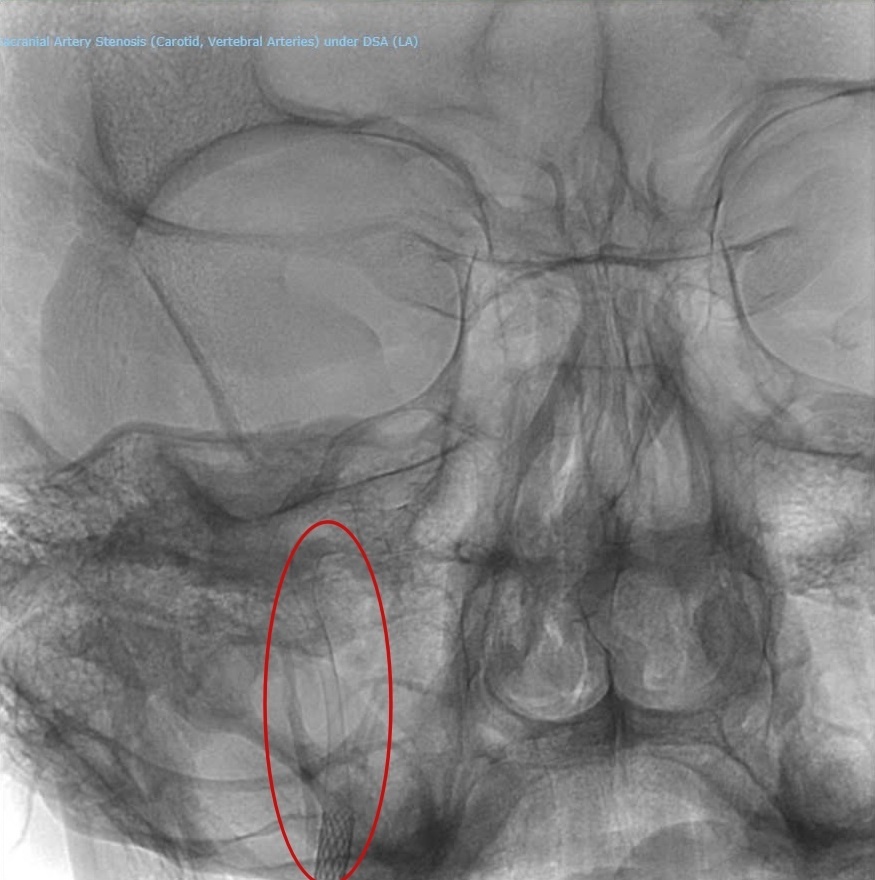

Các bác sĩ phải dùng hai stent chồng nhau để “gia cố” tổn thương dài đến 80 mm.

Trước khi tiến hành thủ thuật, anh A.M được bác sĩ trao đổi kỹ về tình trạng bệnh và phương pháp điều trị. Do vết bóc tách động mạch dài đến 80 mm, nên phải sử dụng hai stent phủ lên nhau để đảm bảo thông thoáng mạch máu.

Thủ thuật do bác sĩ Đức và ê kíp thực hiện diễn ra suôn sẻ trong vòng 3 giờ tại phòng Cathlab, dưới sự hỗ trợ của hệ thống trang thiết bị hiện đại, đặc biệt là hệ thống chụp mạch số hóa xóa nền (DSA) tích hợp đa nhiệm - có thể chụp mạch máu tim, mạch máu não và mạch máu toàn thân. Từ vết rạch ở đùi, bác sĩ đưa ống thông có gắn stent luồn vào động mạch lên đến vị trí động mạch bị rách. Stent được đặt vào vị trí vết rách để “hàn” lại vùng động mạch cảnh, nhờ đó máu có thể lưu thông bình thường trở lại.

| Hình ảnh mạch máu của bệnh nhân sau khi được đặt stent. |